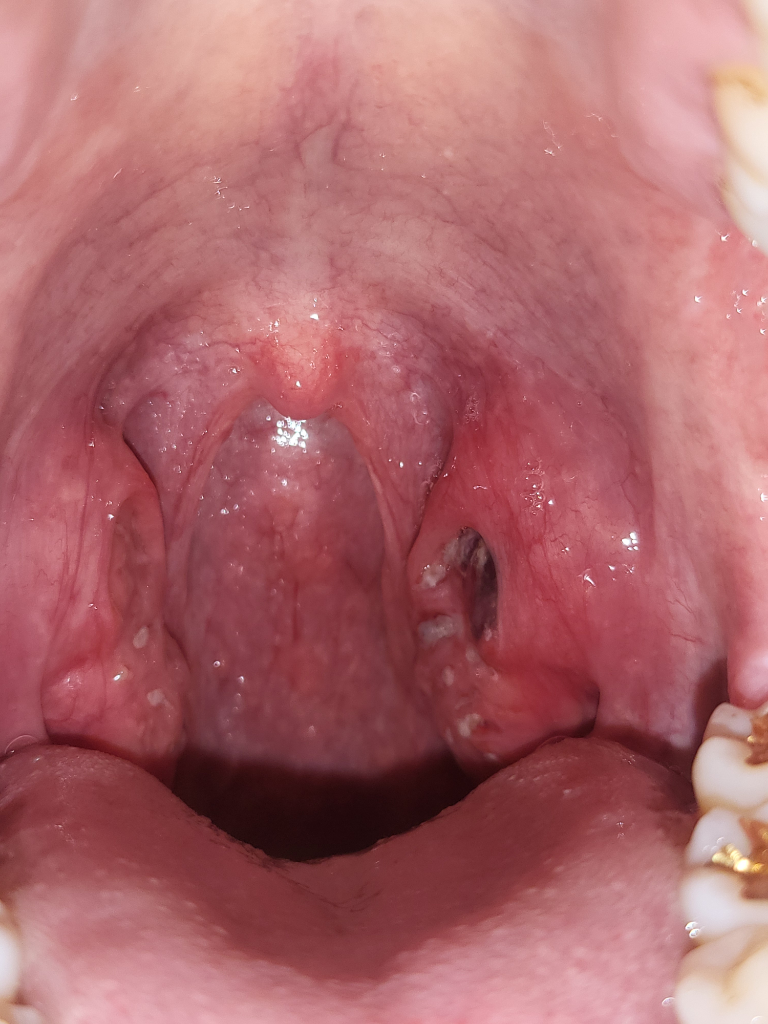

편도에 피가 맺혔는데 이유가 뭔가요?

자고일어나니 편도에 피멍울? 피고름이 생겼습니다.

전날 밤부터 목이 따끔거렸고 자기전에 설사를 했습니다.

면봉으로 닦아보면 피가 맺혀나옵니다.

현재 편도에 부종 및 염증이 있는 것으로 생각됩니다. 출혈, 통증 등의 증상도 이를 시사합니다. 증상이 경미하다면 지켜볼 수 있지만, 불편감이 심하거나 오래 지속되는 경우에는 이비인후과 진료를 받아보시는 것이 좋겠습니다.